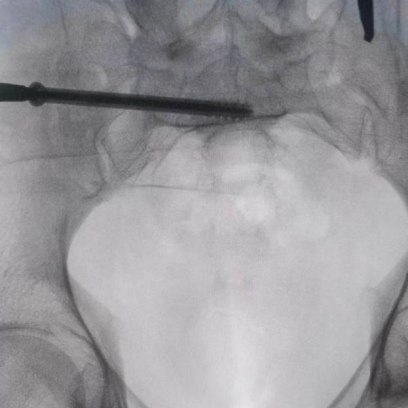

據(jù)了解,患者37歲,為高墜傷患者,入院合并顱腦挫傷、盆腔臟器出血、骨盆骨折多發(fā)傷患者。為最大限度降低手術風險,同時給予患者滿意的手術療效,術前綜合評估患者病情,擬定行“天璣機器人”輔助定位下骨盆骨折微創(chuàng)手術。2月13日10時,手術正式開始。拉薩市人民醫(yī)院采集患者術中二維影像,通過骨科手術機器人擬定螺釘打入位置方向后,吳宏華主任完成手術設計,成功為該患者置入了一顆高難度骶髂螺釘,出血5ml,切口1cm。術后圖像顯示,螺釘位置及方向完全符合手術規(guī)劃,沒有一絲偏差,手術最終獲得圓滿成功。

圖為透視下見置入的骶髂螺釘,位置、長度精準,無絲毫偏差